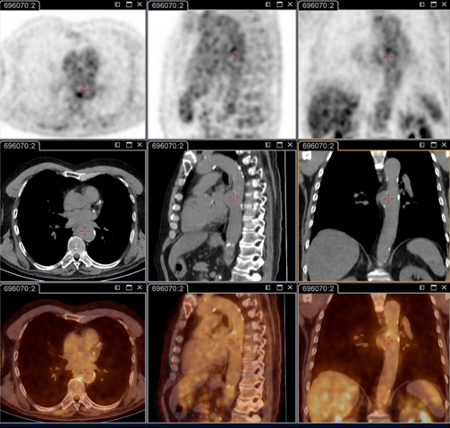

Aneurisma micótico na aorta torácica da febre Q diagnosticado na PET: PET/TC com 18-fluordesoxiglucose. Neste paciente assintomático com história de valva cardíaca e sorologia elevada, a PET permitiu diagnosticar endocardite aórtica na valva nativa com aneurismas micóticos da aorta torácica e lombar

Institut Hospitalo-Universitaire Méditerranée Infection (obtido consentimento do paciente)

Endocardite por febre Q diagnosticada na PET: PET/TC com 18-fluordesoxiglucose. Neste paciente assintomático com história de valva cardíaca e sorologia elevada, a PET permitiu diagnosticar endocardite aórtica na valva nativa com aneurismas micóticos da aorta torácica e lombar

Aneurisma micótico na aorta lombar da febre Q diagnosticado na PET: PET/TC com 18-fluordesoxiglucose. Neste paciente assintomático com história de valva cardíaca e sorologia elevada, a PET permitiu diagnosticar endocardite aórtica na valva nativa com aneurismas micóticos da aorta torácica e lombar